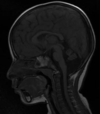

Q

A

Esclerose mesial temporal

Observe a perda de volume, que indica atrofia e causa aumento secundário do corno temporal do ventrículo lateral.

O sinal alto no hipocampo reflete a gliose.

How well did you know this?

Qual o padrão da Esclerose mesial temporal?

Atrofia hipocampal e hipersinal T2. Cerca de 10% dos casos são bilaterais (dificulta o diagnóstico). A etiologia é desconhecida, mas há uma relação entre STM e convulsões febris prolongadas no início da vida A esclerose mesial temporal pode ocorrer em associação com outras patologias, principalmente displasia cortical focal (dual pathology).